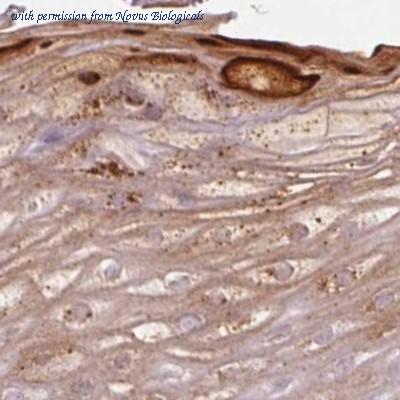

- repetin antibody